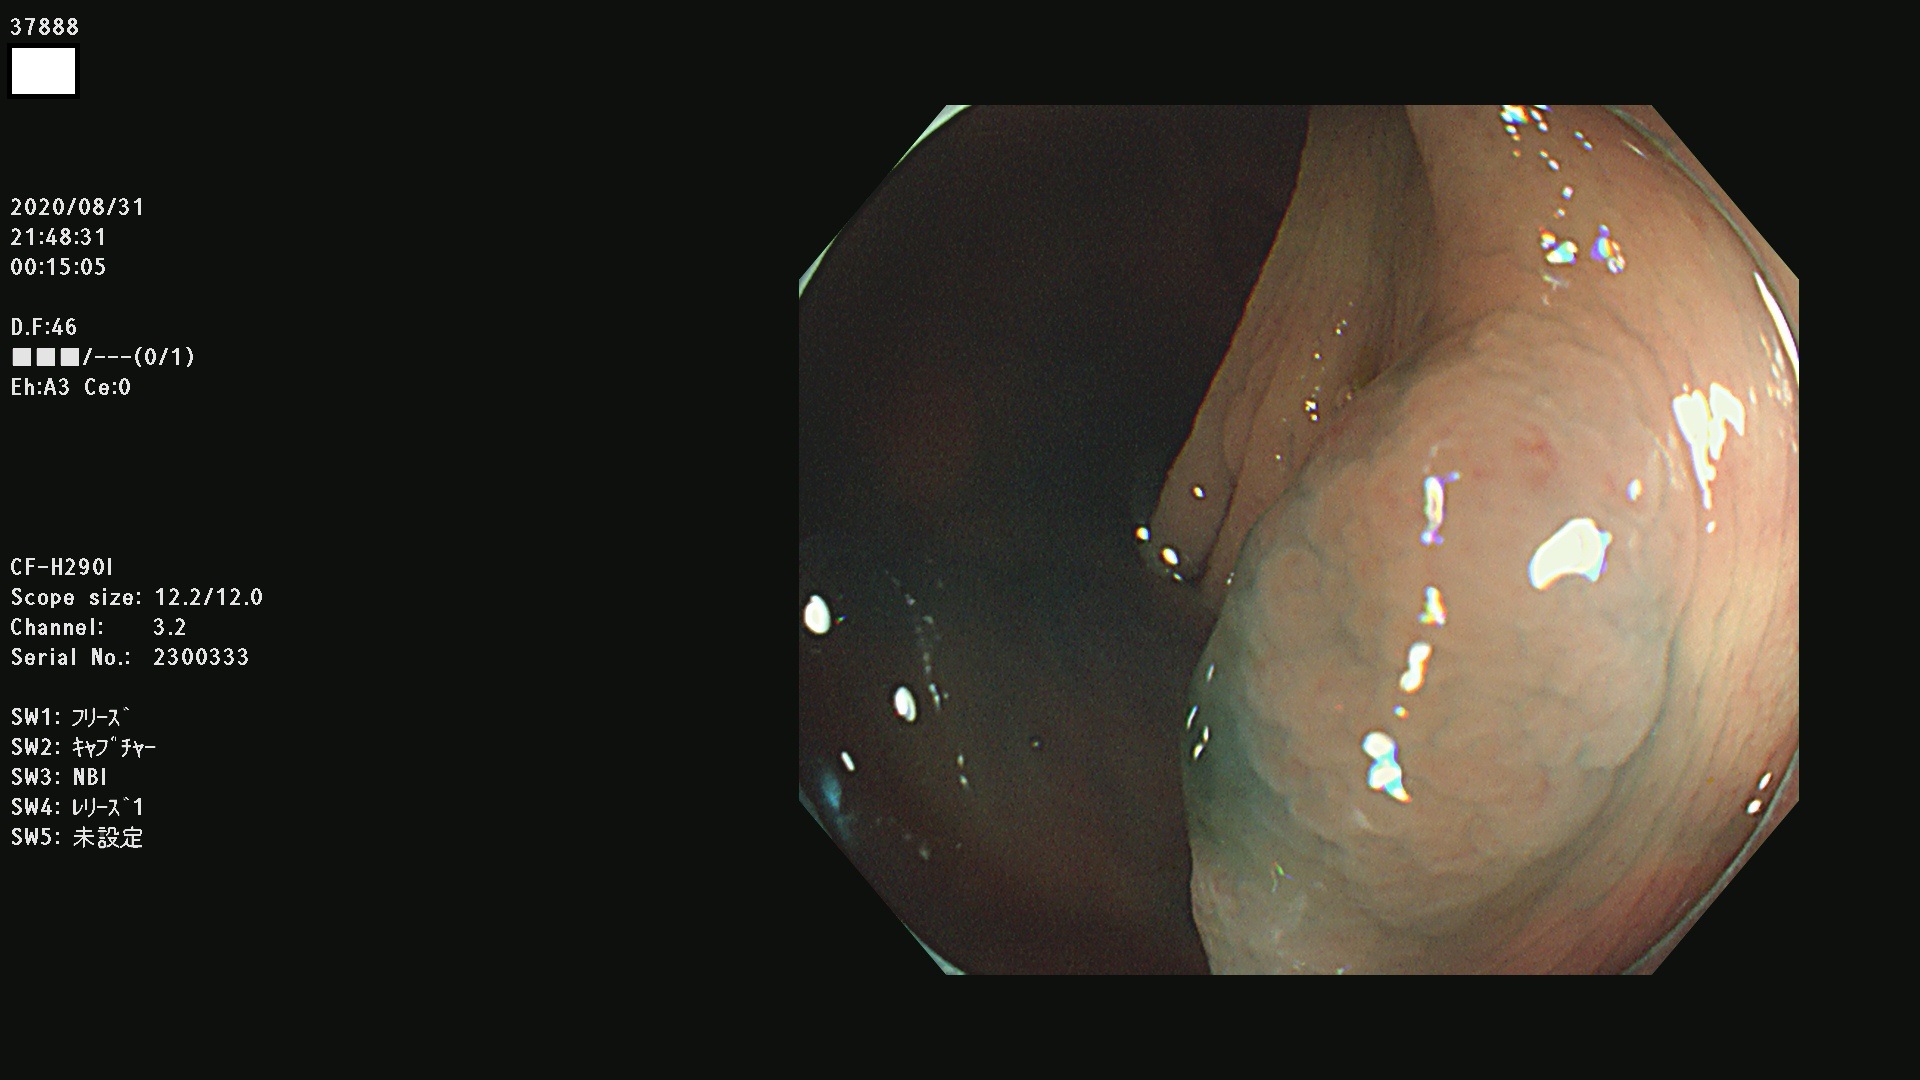

腺腫発見率 75 % (カルテ番号 37800〜37899の100名の方の検査結果で集計)大腸癌検診最新情報

以下のカルテ番号の方に腺腫(Adenoma,Group3〜5)が見つかりました(集計法)

37800(SSAPのみ) 37801 37802 37803 37804 37805 37806 37807 37808 37809(SSAPのみ) 37810 37811 37812 37813 37814 37815 37817 37818 37819 37820 37821 37822 37824 37825 37826 37827 37828 37829 37832 37833 37836 37837(SSAPのみ) 37839 37840 37842 37844 37845(SSAPのみ) 37847 37849 37850 37851 37852 37853(SSAPのみ) 37855 37856 37857 37860 37861 37862 37863 37864 37867 37868 37871 37874 37876 37877 37879 37880 37881 37882 37883 37886 37887 37888 37889 37890 37891 37892 37893 37894 37896 37897 37898 37899

発見困難で危険性の高い平坦型病変(上記100名より抽出) ![]()